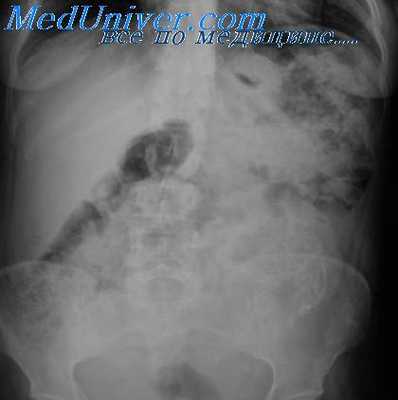

Воспаление дивертикула желудка. Частичное сужение антрального отдела желудка

С присоединением воспалительного процесса в зоне дивертикула появляются отек и перестройка рельефа слизистой оболочки. Контуры его становятся нечеткими и неровными, а сократительная способность стенки снижается. В полости такого дивертикула длительное время (до нескольких часов) задерживается бариевая взвесь, скапливается жидкость, а иногда и газ (симптом «трехслойности»). При повторных исследованиях дивертикул может не выявляться из-за закупорки его отечной слизистой оболочкой, комочками пищи или слизи либо вследствие длительного спазма шейки дивертикула.

В подобных случаях для снятия спазма целесообразно применить соответствующие фармакологические препараты. Дифференцируют дивертикул с язвой, изъязвленным раком и деформациями желудка, обусловленными хирургическим вмешательством, а также другими заболеваниями желудка или соседних с ним органов. Проводя дифференциальную диагностику дивертикула и пептической язвы, необходимо учитывать различия в патологоанатомической сущности обоих процессов, определяющие особенности свойственной им рентгенологической картины. Сужение просвета выходного отдела желудка в этом случае обусловлено своеобразной диафрагмой — мембраной, состоящей из слизистой и подслизистой оболочек, а иногда и гипертрофированной muscularis mucosa (m. propria в образовании диафрагмы обычно не участвует).

Эластичность стенок и их перистальтическая функция не нарушены. При небольших размерах отверстия в диафрагме заполненный бариевой взвесью дистальный отдел желудка может иметь вид второй луковицы (симптом «двойной луковицы»). При этом отчетливо выражены нарушение эвакуаторной функции и дилатация вышележащих отделов желудка, степень которых определяется величиной отверстия в диафрагме. Воспалительные изменения слизистой оболочки обычно отсутствуют. Однако диафрагма желудка может сочетаться с язвой, располагающейся вблизи мембраны с проксимальной или дистальной ее стороны, а также с чреспривратниковым выпадением слизистой оболочки.

Частичное сужение дифференцируют от патологически измененной поперечно идущей складки слизистой оболочки антрального отдела, перигастральных спаек, «шнурующей» перистальтической волны и локального спазма.